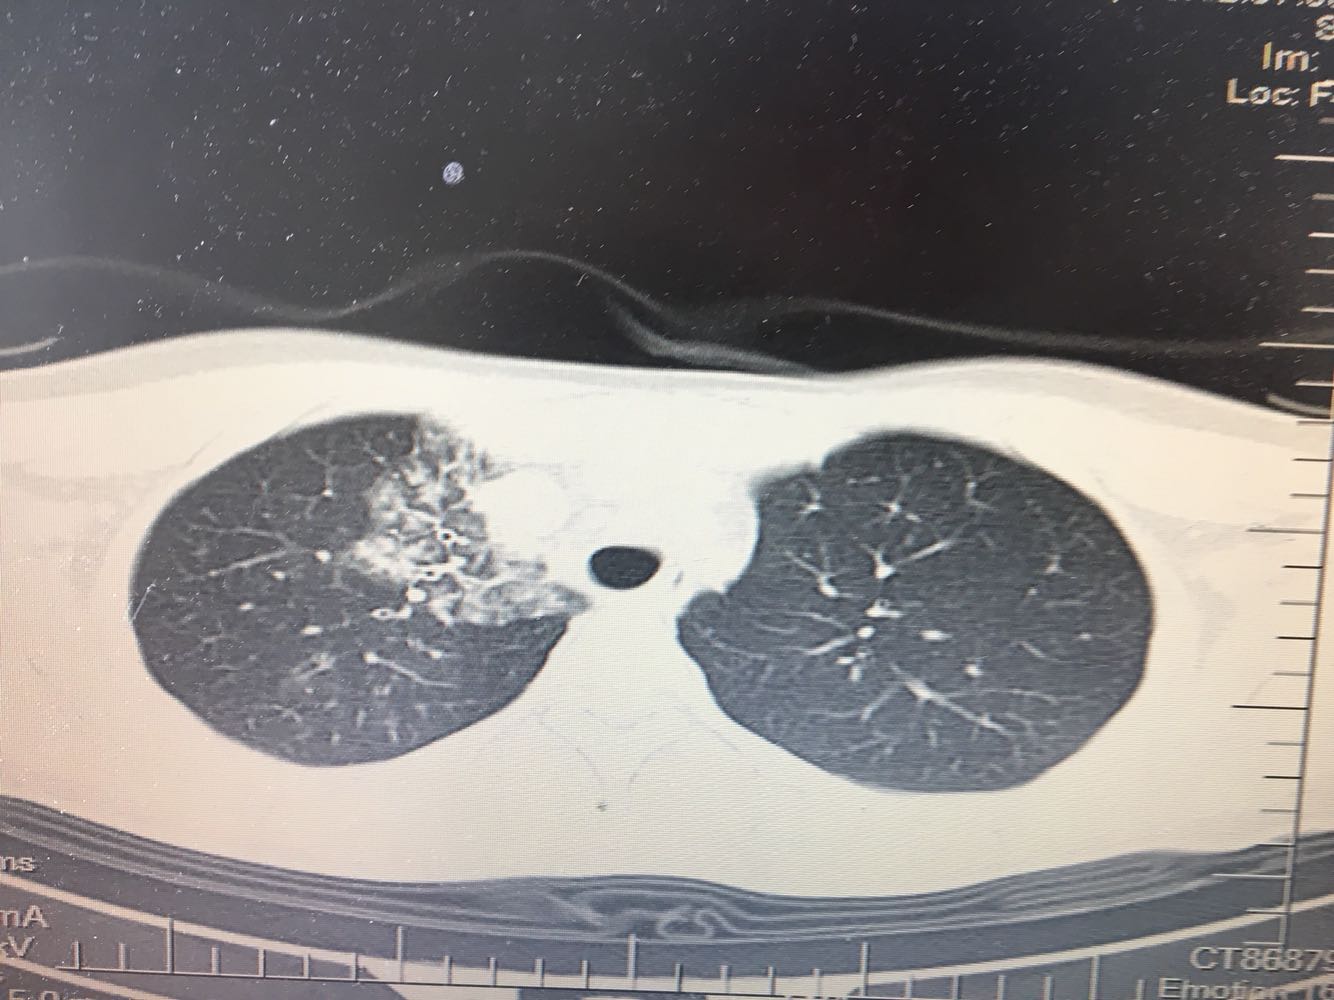

支原体肺炎?肺结核?

女,26岁,咳嗽1周,咳痰不畅,咽喉痒,口服阿莫西林无好转,昨日发热,体温38.5摄氏度,于门诊查肺CT后以肺炎收入院,病来无盗汗,无咳血,无消瘦及乏力,无头痛,无肢体酸痛,饮食睡眠可,二便正常

支原体抗体1:160,结核抗体弱阳性。支原体肺炎个别可见上叶病变,该患无结核中毒症状,考虑支原体肺炎可能性大,但肺尖为结核好发部位,需要抗炎治疗后复查观察疗效。